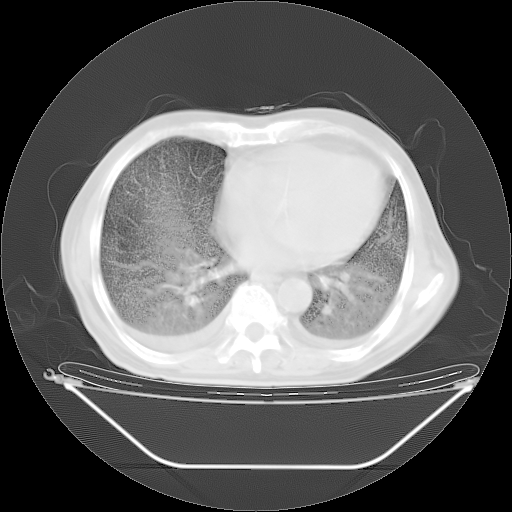

今天复查肺部CT,发现双肺广泛磨玻璃样改变。所以我把3月19日和5月9日相隔50天的肺部CT上传。请大家会诊。

5月9日肺部CT(在4月27日齐鲁医院肺部CT描述部分肺组织磨玻璃样改变,12天后肺组织广泛磨玻璃样改变)

大致读了系列胸部CT:纵隔窗无明显异常,肺窗:从4、27至今:主要是双肺中下野外带可见毛玻璃样改变,目前处于急性肺泡炎阶段,至于原因考虑1、结替组织或胶原血管性疾病所致?2、恶性疾病如恶组在肺部所致的表现或细支气管肺泡癌?3、药物或其它原因如肺蛋白沉着症所致肺泡炎目前不太可能?总之,明天就去请我院的呼吸科、感染科、血液科和临免专家会诊哈。